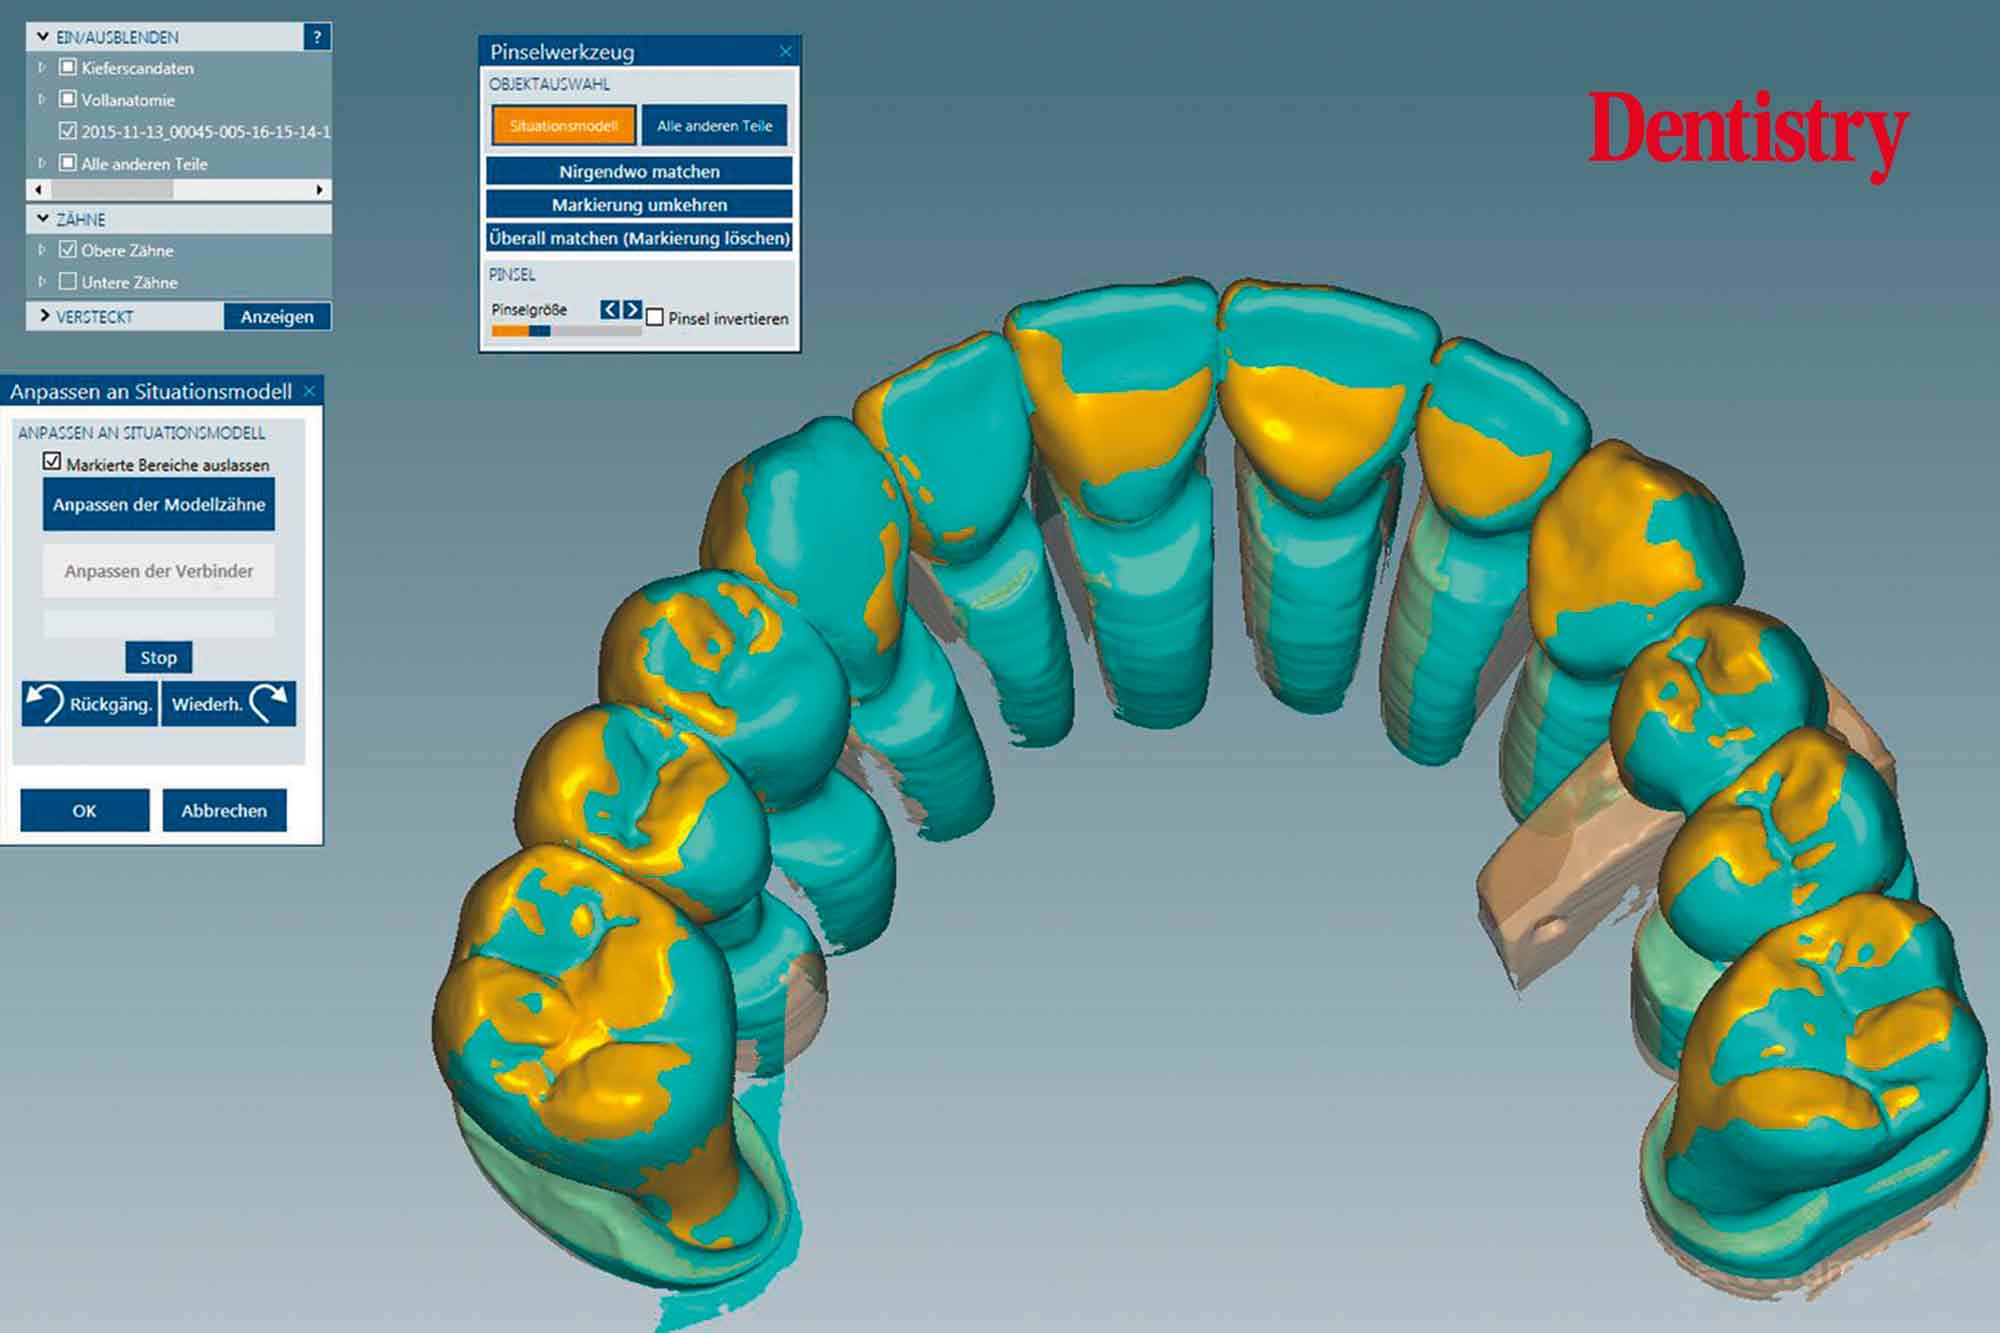

CAD design of the final crowns

Using the CAD software (Figure 12), we were able to round off and refine the areas on the temporary crowns that had been ground and modified intraorally. As a result, this left the remaining areas unchanged.

Figure 13 shows the areas that were adjusted intraorally in green and the remaining unchanged areas in blue. The plan was to fabricate Ceramill Zolid FX crowns on the maxillary teeth first. This is so subsequent corrections on the lower temporary crowns would mean that less corrections would be necessary for the final lower crowns.